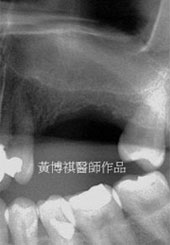

手術區域為上顎後牙區,先游離上顎骨後,進入鼻竇腔進行骨再生術式術後X光片可見上顎骨墊 出一層厚厚的新骨,術後一年追蹤,骨細胞逐漸生成新的上顎骨。 |